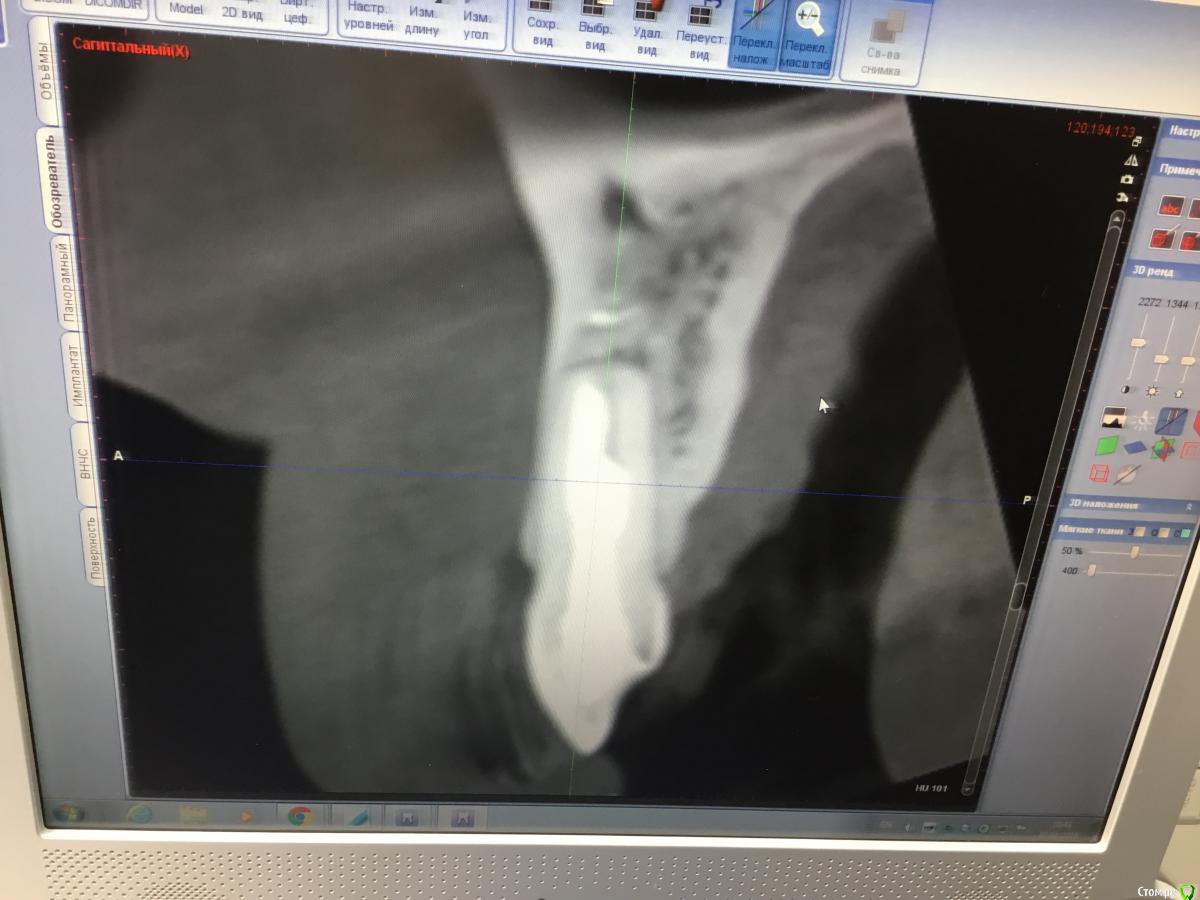

Zorrro Опубликовано 6 марта, 2016 Поделиться Опубликовано 6 марта, 2016 (изменено) Мой постоянный пациент привёл своего сынишку с жалобами на свищь на нёбе.Сделали кт и решили ,что вначале переберём каналы,а через пол года будем посмотреть куда нам двигаться дальше… Эстетика коронки на 11 вполне устраивала пациента,тем более он был уверен,что поставилимплант и вследствии коронку популярный доктор используя новейшие технологии и материалы,позволяющие не прибегать к устаревшим костным и ещё каким-то пластикам.запись к доктору уходила на пол года вперёд и молодой человек чудом втиснулся в этот плотный график,чтобы отхватить немножко и себе этих самых "новейших" технологий под нос. Фото ещё раз показывает,чтосамое главное в успехе частной практики это ВЕРА доктора в себя и то,что он делает.меня же коронка устраивала тем более,потому что переделывать её вместе с имплантом мне крайне не хотелось.обошлись комментарием про усиленную гигиену и регулярные наблюдения раз в пол года. итак занялись посильным трудом:отмыли 21 и 22,констрикция убежала за 50.02,остановились на 70.02 стальными файлами отступя 1мм,метапекс,через 2 недели irm и стекловолокно нафуджи+,филтек.договорились про контроль через пол года и коронки если всё ок. Ещё немного срезов до и преимущество кт перед прицельными снимкамиИ сразу после. Про коронки и корневой герметизм пациент не понял и решил оставить бломбы на месте. Изменено 6 марта, 2016 пользователем Zorrro 1 Ссылка на комментарий